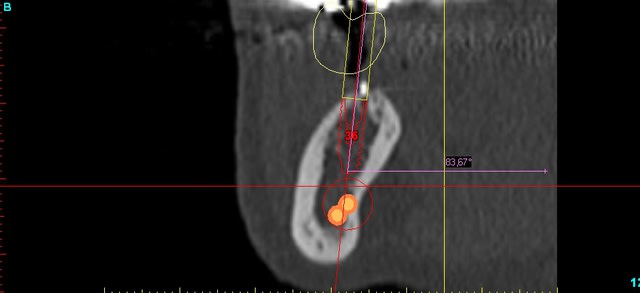

Bonjour, pour un implant au niveau de 36, la tomo montre un deuxieme canal plus haut que le V3. Pour le radiologue pas de soucis . Mais c pas lui qui pose donc ... qu'en pensez vous, sachant que je suis obligé de le léser si je pose!!

voila les coupes en 36. A la retro je ne vois rien , et la pano c pas vraiment net

je pencherais plutôt pour le paquet vasculaire qui accompagne le NDI...fais voir les coupes qui précèdent, depuis l'épine de spix...

ok , je t envoie ca ce soir aprés le cab. Mais moi aussi j'ai l'impression qu il y a un os!! Pour le radiologue , je l ai appele il me dit qu'avec la precision des tomo qui augmente , il trouve de plus en plus de canaux accesoires, et au vue du diametre ca ne serait pas de branches motrices... et comme tu peux comprendre ca ne m'a pas convaincu.

c'est pas très claire sur la tomo:

largeur des coupes ?

position de 37 et 35 par rapport à l'édentement ?

C'est pas simplement le pédicule vasculo-nerveux de feu 36 ???